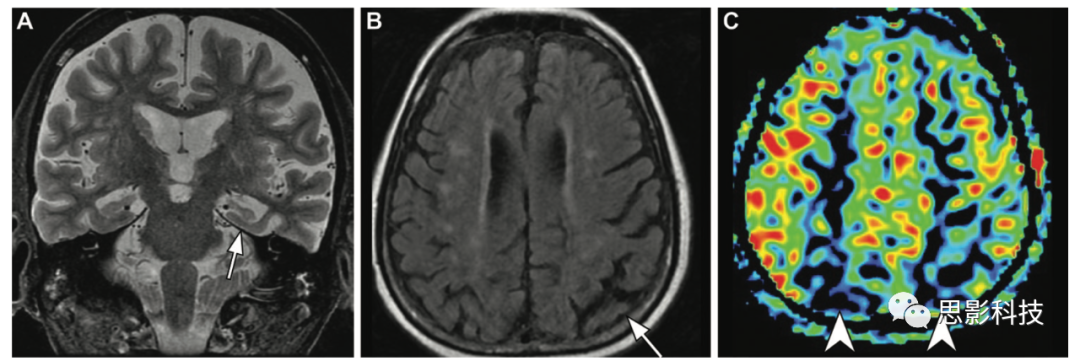

血管母細(xì)胞瘤 血管母細(xì)胞瘤是一種高度血管化的低級(jí)別腫瘤,通常表現(xiàn)為囊性病變,伴有顯著增強(qiáng)的壁結(jié)節(jié)或?qū)嵭圆∽儯T诤箫B窩內(nèi)含有血流空隙(60%的患者)。它可以作為孤立性病變或多發(fā)性病變發(fā)生,也可以與其他內(nèi)臟腫瘤合并,作為von Hippel-Lindau綜合征的一部分(14)。血管母細(xì)胞瘤的絕對(duì)和相對(duì)TBF較高,TBF總血流量明顯高于膠質(zhì)瘤、腦膜瘤和神經(jīng)鞘瘤。

14 48歲男性von Hippel-Lindau綜合征患者的小腦和視網(wǎng)膜血管母細(xì)胞瘤。

(A)軸位高分辨率增強(qiáng)后T1加權(quán)成像顯示右側(cè)小腦邊界清晰的均質(zhì)囊變(低信號(hào)區(qū)域),壁結(jié)節(jié)明顯強(qiáng)化,代表一個(gè)小腦血管母細(xì)胞瘤(白色箭頭),另外兩個(gè)小血管母細(xì)胞瘤(箭頭),以及一個(gè)左眼有強(qiáng)化病變的視網(wǎng)膜血管瘤(黑色箭頭)。

(B)ASL MRI顯示所有四個(gè)血管母細(xì)胞瘤的實(shí)體成分(白色和黑色箭頭)的灌注增加,可與單純囊性病變(低信號(hào)區(qū)域)相區(qū)別。

繼發(fā)性腫瘤 幾個(gè)腦轉(zhuǎn)移病變表現(xiàn)出高TBF,可能類似于高級(jí)別膠質(zhì)瘤,如腎細(xì)胞癌、血管肉瘤、血管母細(xì)胞瘤和黑色素瘤。ASL MRI灌注成像中,高級(jí)別膠質(zhì)瘤在瘤內(nèi)和瘤周的TBF明顯高于轉(zhuǎn)移瘤。Solozhent seva等人在高級(jí)別腦膠質(zhì)瘤中的絕對(duì)TBF和相對(duì)TBF均顯著高于腫瘤內(nèi)轉(zhuǎn)移者(絕對(duì)TBF68.98±91.96 vs1 52.1±173.32;相對(duì)TBF7.6±8.4 vs 9.3±5.33P<0.01)和瘤周(絕對(duì)TBF29.61±22.89 vs 16.58±6.46;相對(duì)TBF1.63±1.14 vs 0.88±0.38P<0.01)。在成人后顱窩腫瘤的鑒別診斷中,ASL也有助于區(qū)分轉(zhuǎn)移瘤和血管母細(xì)胞瘤。Kang等人的研究表明,血管母細(xì)胞瘤的大小和相對(duì)輸出量顯著大于轉(zhuǎn)移瘤。ASL灌注也有助于發(fā)現(xiàn)顱骨轉(zhuǎn)移。